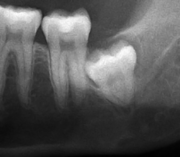

For partially impacted teeth in those over 20 year of age, the most common pathology seen, and the most common reason for wisdom teeth removal, is pericoronitis or infection of the gum tissue over the impacted tooth. The bacteria associated with infections include Peptostreptococcus, Fusobacterium, and Bacteroides bacteria. The next most common pathology seen is cavities or tooth decay. Fifteen percent of people with retained wisdom teeth exposed to the mouth have cavities on the wisdom tooth or adjacent second molar due to a wisdom tooth. The rate of cavities on the back of the second molar has been reported anywhere from 1% to 19% with the wide variation attributed to increased age.[10]

In five percent of cases, advanced periodontitis or gum inflammation between the second and third molars precipitates the removal of wisdom teeth.[3]:141[4] Among patients with retained, asymptomatic wisdom teeth, roughly 25% have gum infections (periodontal disease).[11]:ch13 Teeth with periodontal pockets of greater than 5mm have tooth loss rates that start at 10 teeth lost per 1000 teeth per year at 5mm to a rate of 70 teeth lost per year per 1000 teeth at 11mm.[12]:57 The risk of periodontal disease and caries on third molars increases with age with a small minority (less than 2%) of adults age 65 years or older maintaining the teeth without caries or periodontal disease and 13% maintaining unimpacted wisdom teeth without caries or periodontal disease.[13] Periodontal probing depths increase over time to greater than 4 mm in a significant proportion of young adults with retained impacted wisdom teeth which is associated with increases in serum inflammatory markers such as interleukin-6, soluble intracellular adhesion molecule-1 and C-reactive protein.[14]